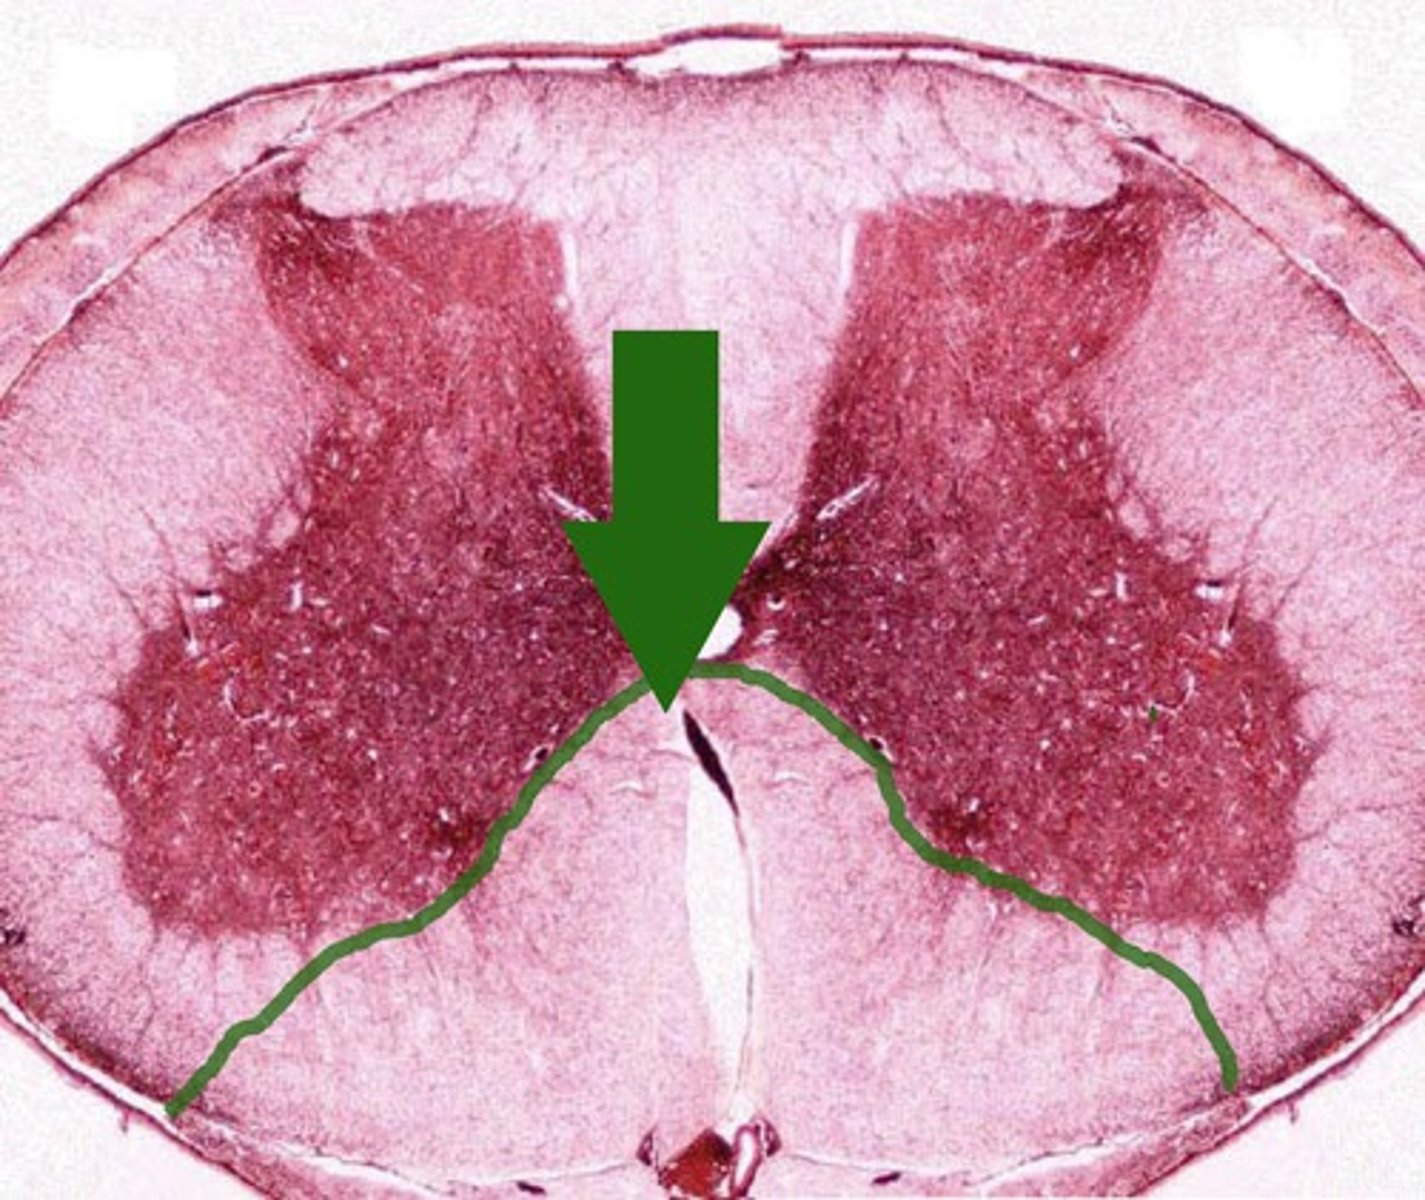

Gray Commissure

6

Central Canal

5

White Matter

7

Posterior funiculus

8

Anterior Funiculus

9

Lateral Funiculus

10

Anterior Median Fissure

B

anterior horn

E

posterior horn

f

lateral horn

g